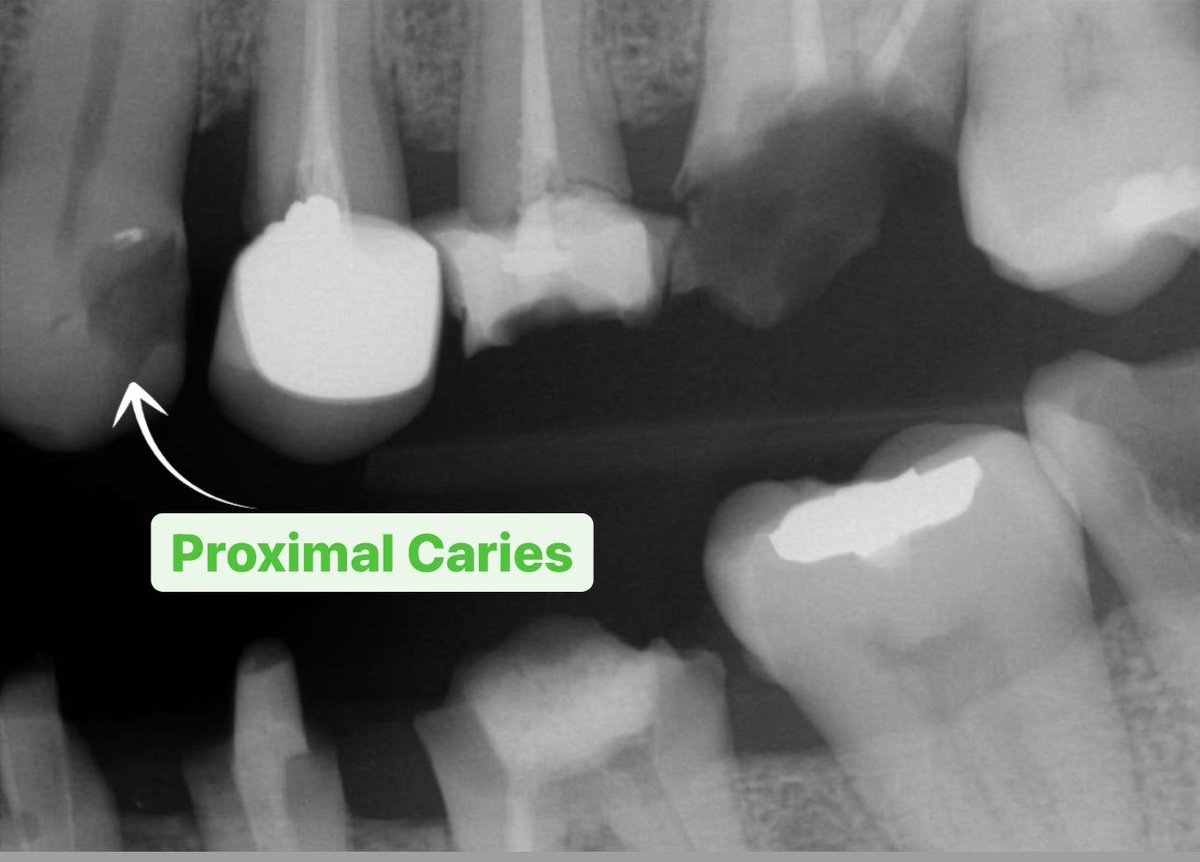

🟢لا تاخذ فاينل امبريشن لكراون و بجنبه سن محتاج class II ..النتيجة راح تغري تلبيستك و يسوون الحشوة و يخرب ال proximal surface حقها..ليش؟ حرام.

🟢لا تعتمد على أشعة زاويتها غلط لتقييم ال crowns fit or abutment fit ثمن تواصل، و في أشعة جديدة صحيحة تشوف المشكلة! ابدأ بالزاوية العمودية الصح من البداية و ارتاح >> bitewing + parallel PA